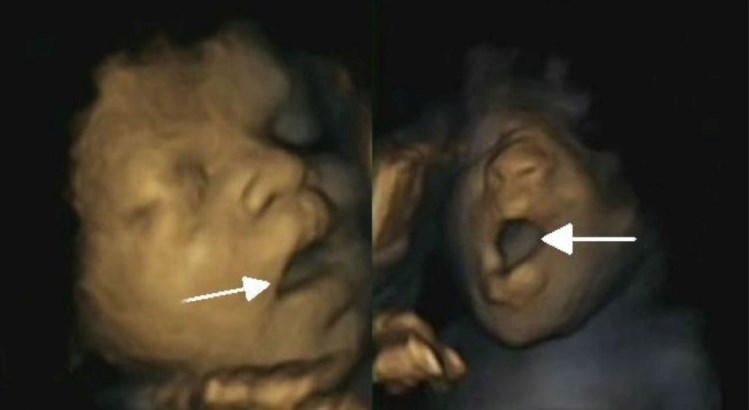

O feto a abrir a boca (à esquerda) e a bocejar, numa imagem captada pela equipa britânica DR

Os vídeos provam-no: o bebé, ainda na barriga da mãe, já boceja. À medida que o feto se vai desenvolvendo e a gestação se aproxima do fim, os bocejos decrescem e não há grandes diferenças entre rapazes e raparigas na frequência com que o fazem.

A equipa liderada por Nadja Reissland, do Departamento de Psicologia da Universidade de Durham, estudou 15 fetos – oito raparigas e sete rapazes –, com idades de gestação entre as 24 e as 36 semanas. No total, fizeram 58 ecografias, que permitiam obter gravações em vídeo dos fetos, os cientistas puderam distinguir entre um bocejo (56) e a mera abertura da boca (27) e confirmaram a existência deste movimento nas nossas vidas desde tão cedo.

No bocejo, considera-se que a boca se mantém aberta mais tempo no início do que na parte final. Além desta perspectiva dinâmica do bocejo, difícil de captar noutras ecografias bidimensionais, a sua definição ainda inclui a abertura dos maxilares, uma inspiração profunda, seguida de uma curta expiração, antes de a boca se fechar.